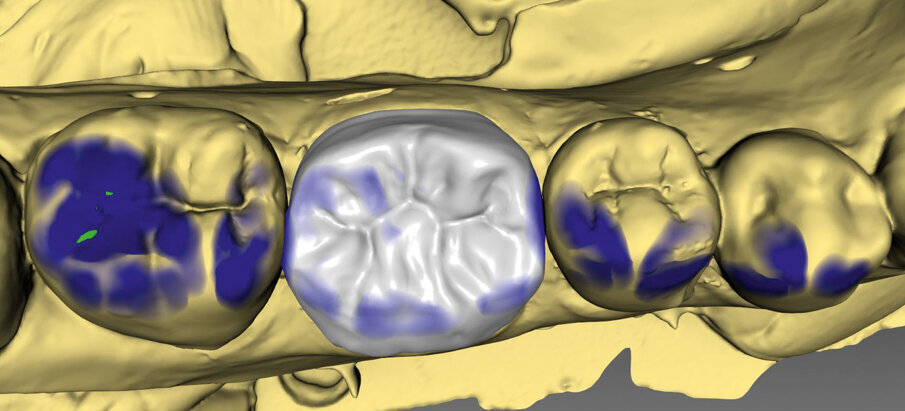

Fig. 3a: Crown design in the software suite (Cerec inLab) and try-in before crystallization firing (IPS e.max)

Fig. 3b: Crown design in the software suite (Cerec inLab) and try-in before crystallization firing (IPS e.max)

A 45-year-old male patient presented to the practice with a restoration on tooth 46. The tooth had been endodontically treated and was temporized with a filling (Fig. 1). The temporary was removed, the tooth built up with Tetric N-Ceram Bulk Fill and then prepared for the crown restoration (Fig. 2). An impression was taken with a one-step two-phase impression technique using putty and light-body silicone. After scanning the model, the crown was designed in the software suite (inLab, Dentsply Sirona) and milled from an IPS e.max® lithium disilicate block (Fig. 3). After the crystallization firing the crown was stained and glazed (Fig. 4).